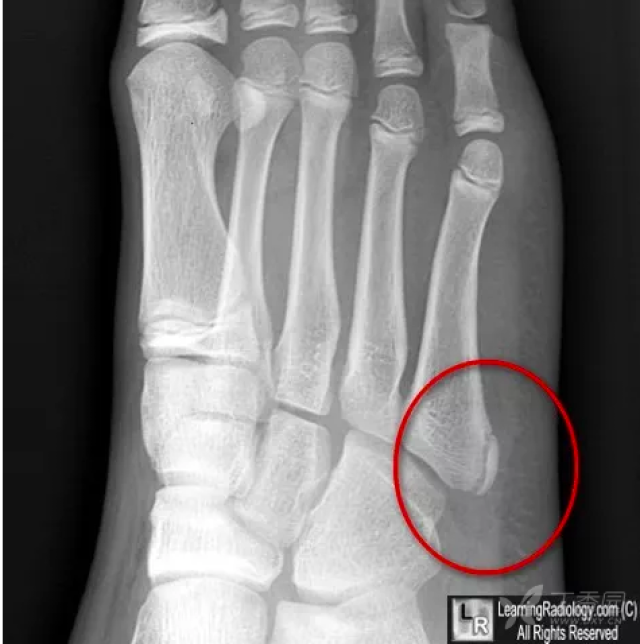

第五跖骨基底部骨折丨表现分型鉴别